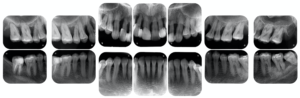

患者様はまだ30代の女性です。初診時には上の歯ぐきから膿が出てグラグラしている歯が多数認められました。

上の歯は歯を支える骨がかなり溶けてしまっています。でも痛みなどの自覚症状はほとんど無かったのです。このまま放置しておいたらほとんどの歯が数年後に抜けてしまっていたと思われます。

歯を支える骨が随分溶けてしまってます。この部分を綺麗にお掃除してリグロスのお薬を入れ、歯ぐきを元どおりに戻します。

治療して被せ物をする前のレントゲン写真です。

治療前に比べてだいぶ骨が再生しているのが確認できました。